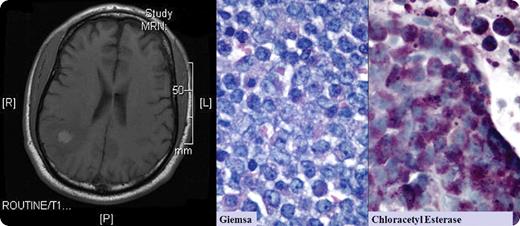

A 56-year-old man had a history of acute promyelocytic leukemia and had been in remission for 2 years. He developed the new onset of seizures. Brain MRI showed 2 well-circumscribed right parietal lobe lesions (one lesion shown above). Spinal fluid cytology was negative for malignant cells. Bone marrow aspiration and biopsy were negative. The neurosurgeon resected these lesions that were within brain tissue and distinct from the meninges. Microscopic review revealed an infiltrate of immature cells, CD10- and CD117-positive, and containing granules that appeared as promyelocytes.

Granulocytic sarcomas are rare collections of acute leukemic cells that can occur in any soft tissue area, including bone, skin, lymph nodes, breast, ovary, meninges, orbit, and optic nerve. In early reports, they were known as chloromas, because of their rich myeloperoxidase content that appeared green. Granulocytic sarcomas appear in individuals who have normal marrows. They usually precede marrow involvement by acute leukemia or chronic myelogenous leukemia by months to years.